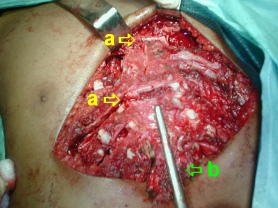

Intervención quirúrgica

• Ténica Ravicht modificada:

• Incisión sub-mamaria transversa.

• Disección muscular de ambos pectorales, permite la exposición de la pared costal costal anterior, desde el manubrio hasta el sifoides.

• Desperiostización y resección de III arco al X arcos cartilaginosos bilaterales.

• No fue necesario condroplastia del los segundos arcos costales.

• Dos osteotomias transversas fueron necesarias para corregir la deformidad esternal, se fijan mediante sutura alambre No.5 puntos X.

• La resección del sifoides se realiza a continuación.

• Se fijan los pectorales y se reinserta el recto anterior del abdomen.